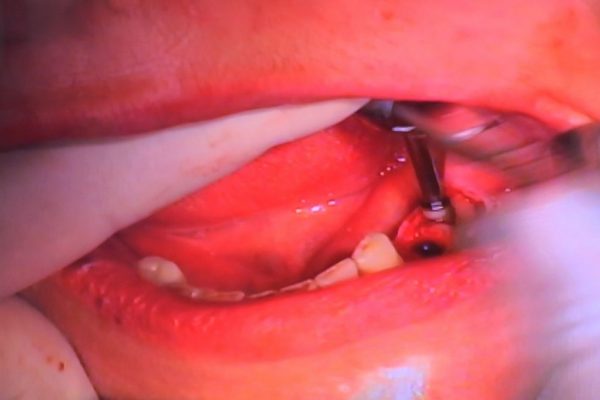

W ostatni weekend czerwca 2018 roku kursanci II Sezonu Preludium Implantologii odbyli piątą, finałową sesję, która w całości podporządkowana była praktyce. W ciągu dwóch dni zabiegowych Lekarze uczestniczący w szkoleniu przeprowadzili szereg zabiegów pod kierunkiem dr n.med. Violetty Szycik. Wszczepili 17 implantów oraz przeprowadzili ekstrakcje i zabiegi regeneracyjne kości. Zabiegi były wykonywane także w sedacji dożylnej z udziałem specjalisty anestezjologii i intensywnej terapii dr Jolanty Grzybowskiej. Preludium implantologii to nowy program edukacyjny dla adeptów implantologii stomatologicznej, którego celem jest wprowadzenie do implantologii poprzez pozyskanie wiedzy w szerokim zakresie i uwzględnieniem szczegółów mających decydujące znaczenie dla powodzenia leczenia implantologicznego. Ale tak jak wszystkie szkolenia w Instytucie Vivadental, w tym wiodące Practiculum Implantologii, zorientowane jest na praktyce i samodzielnym wykonywaniu zabiegów pod kierunkiem Mentora. To najlepsza edukacja w medycynie zabiegowej, a zarazem najlepszy start do implantologii.